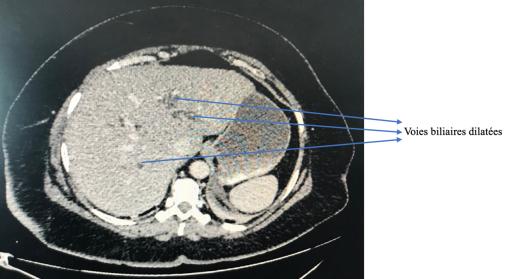

PACS CHSD, La Revue du Praticien Foie homogène avec voies biliaires trop bien visibles, ce qui signifie qu’elles sont dilatées. Extrait de : Dossier progressif n°160